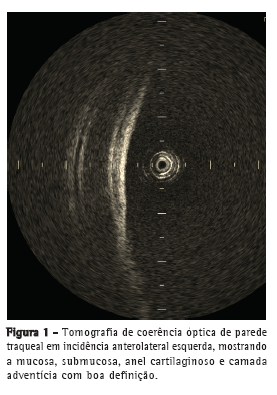

A OCT foi capaz de delinear, em tempo real, microestruturas, tais como epitélio, submucosa, cartilagem e camada adventícia (Figura 1) das paredes anteriores e laterais da traqueia de forma semelhante às imagens histológicas (Figura 2). Na parede posterior, as camadas correspondentes à mucosa, submucosa e musculatura traqueal foram claramente diferenciadas na OCT (Figura 3) e condizentes com a imagem histológica (Figura 4).

A OCT permitiu a identificação, em tempo real, de microestruturas, tais como epitélio, submucosa, cartilagem e camada adventícia nas paredes anteriores e laterais da traqueia. Na parede posterior, foi possível identificar mucosa, submucosa e musculatura traqueal.

Nossos resultados mostraram que a OCT foi capaz de gerar imagens de alta resolução da mucosa, submucosa, cartilagem e camada adventícia traqueais, incluindo microestruturas, como epitélio e pericôndrio, prescindindo de contato entre o cateter e a traqueia, dados esses compatíveis com os da literatura.(5,13)